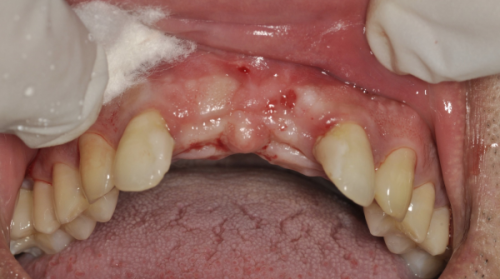

口腔健康状况对种植牙寿命的影响

自身的口腔健康状况也会影响牙齿种植能用多久。如果本身患有牙周病、龋齿等口腔疾病,种植牙的使用寿命可能会受到影响。牙周病会导致牙龈萎缩、牙槽骨吸收,从而使种植牙失去稳定的支撑;龋齿则可能引发牙齿疼痛、感染等问题,波及种植牙。所以,在进行牙齿种植前,更好先治疗好现有的口腔疾病。在种植牙使用过程中,也要定期到牙医处检查,及时发现和治疗新出现的口腔问题。